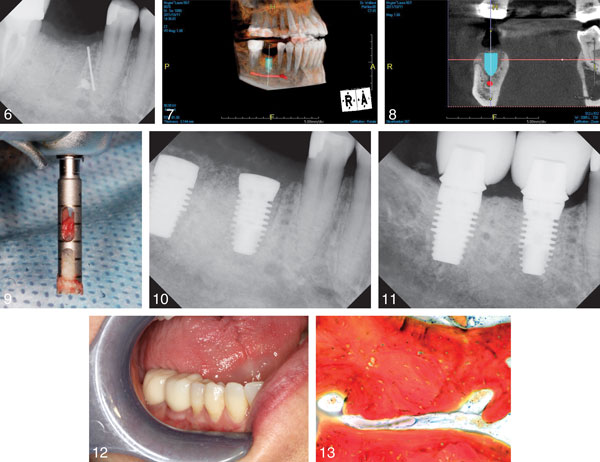

This case series examines a new ADM replacement material called decellularized dermis matrix (DDM) that, combined with mineralized bone grafts called mineralized cancellous bone allograft (MCAB), guides the regeneration of bone to allow for a more stable placement of the implant. This method has a higher regeneration percentage and supports a more stable future implant site than previous therapies.

Tissue samples were examined both microscopically and using 3D imaging. Valuable surgery preparation time was saved using DDM, which can be stored fully hydrated, and the material was easy to handle and adapted well to the shape of extraction-site defects. A minimum of 12 weeks post extraction, the study found that none of the molar extractions had developed infections. A loss of bone volume was also prevented, allowing for optimal implant placement and stability. These results demonstrate the value of DDM and MCAB in preparing molar extraction sites to support implant placement.